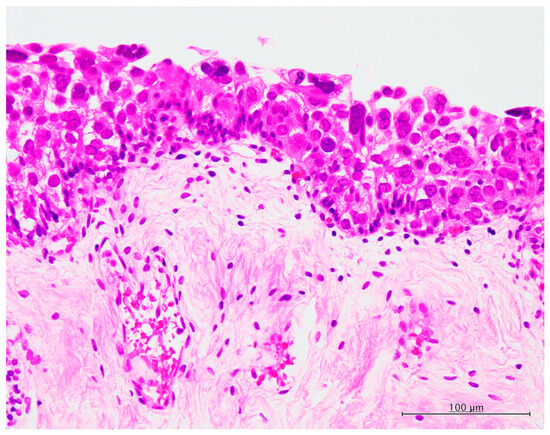

3.2. Histopathological and Immunohistochemical Features